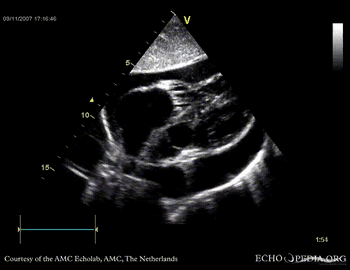

Case 14

Tamponade

Courtesy of:

J. Vleugels, AMC, The Netherlands

tamponade 4